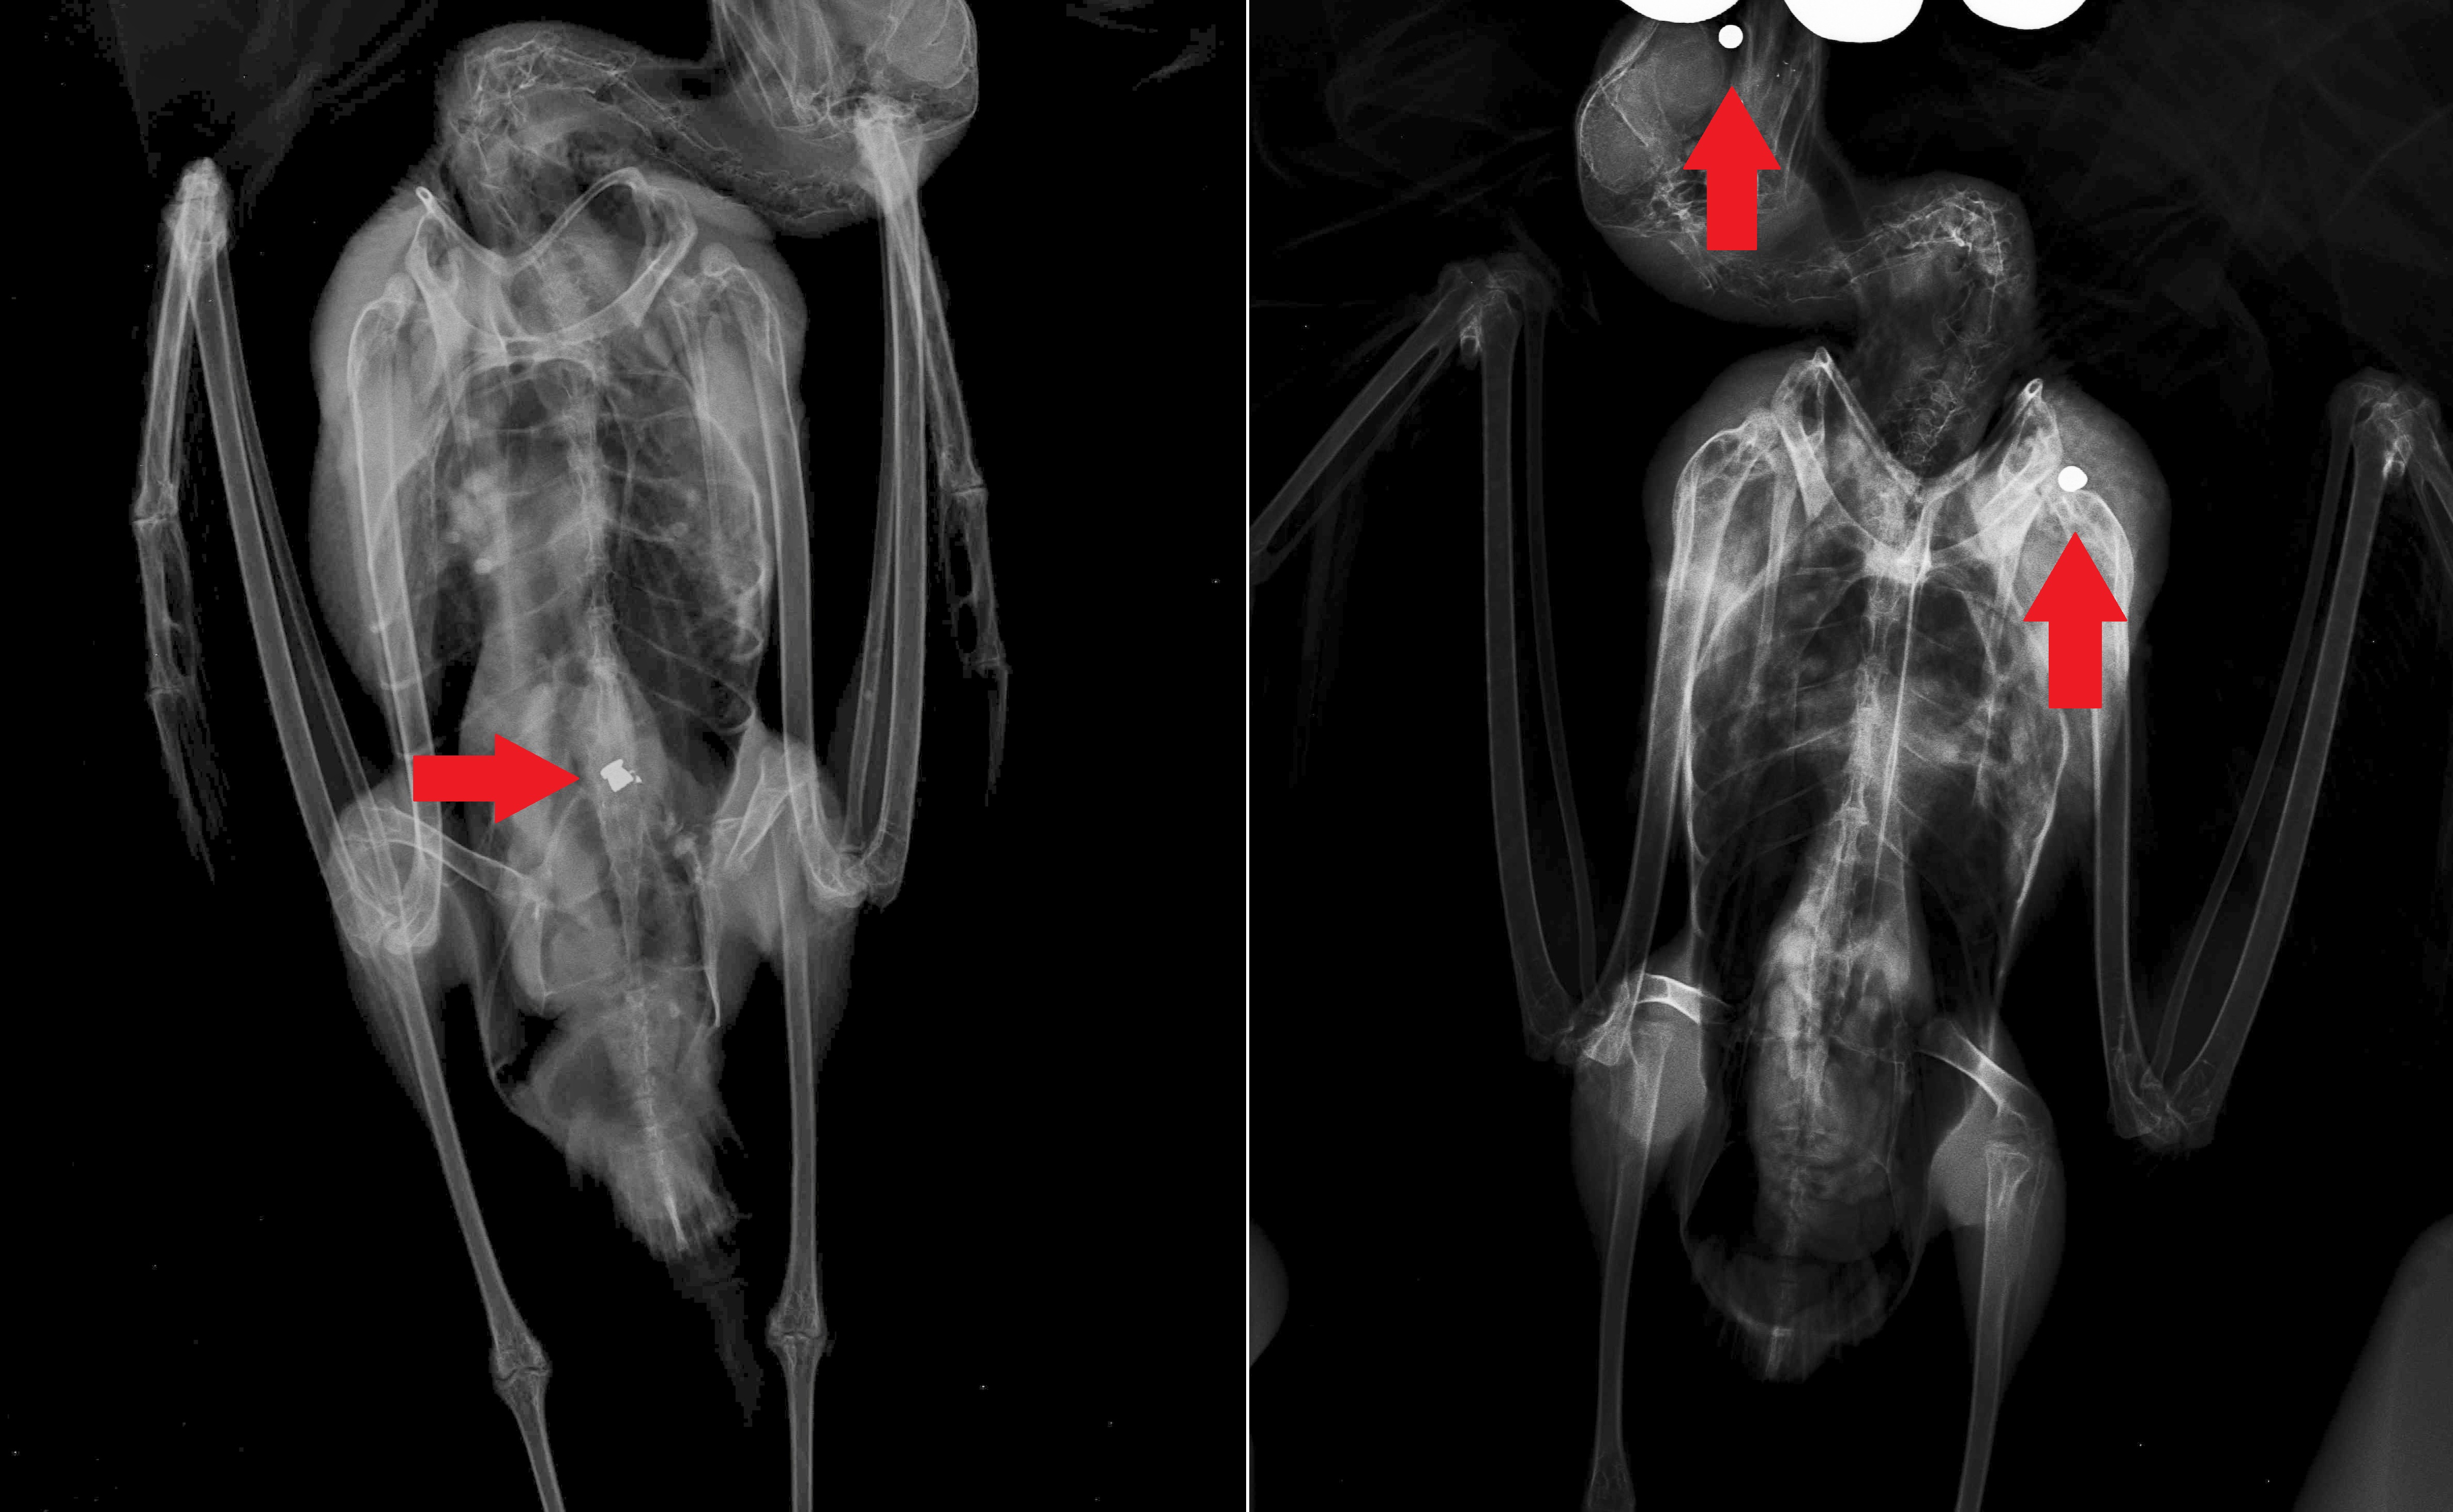

Duas destas aves eram gaivotas-de-patas-amarelas (Larus michahellis). Uma delas continha um chumbo na zona lombar da coluna (imagem em baixo, à esquerda) e a outra, na cabeça e ombro (imagem em baixo, à direita).

Infelizmente, a localização do chumbo numa destas gaivotas, causou uma lesão medular irreversível que a impossibilitava de caminhar de forma permanente. Sem possibilidades médicas para devolver ao animal a sua autonomia, a equipa veterinária decidiu que deveria ser administrada eutanásia, terminando o sofrimento e angústia causados a esta gaivota.

Também a outra gaivota acabou por não resistir aos graves ferimentos provocados pelos projécteis que frequentemente causam infecções na zona atingida.

| Raio-x de duas gaivotas, onde é possível observar os chumbos. |